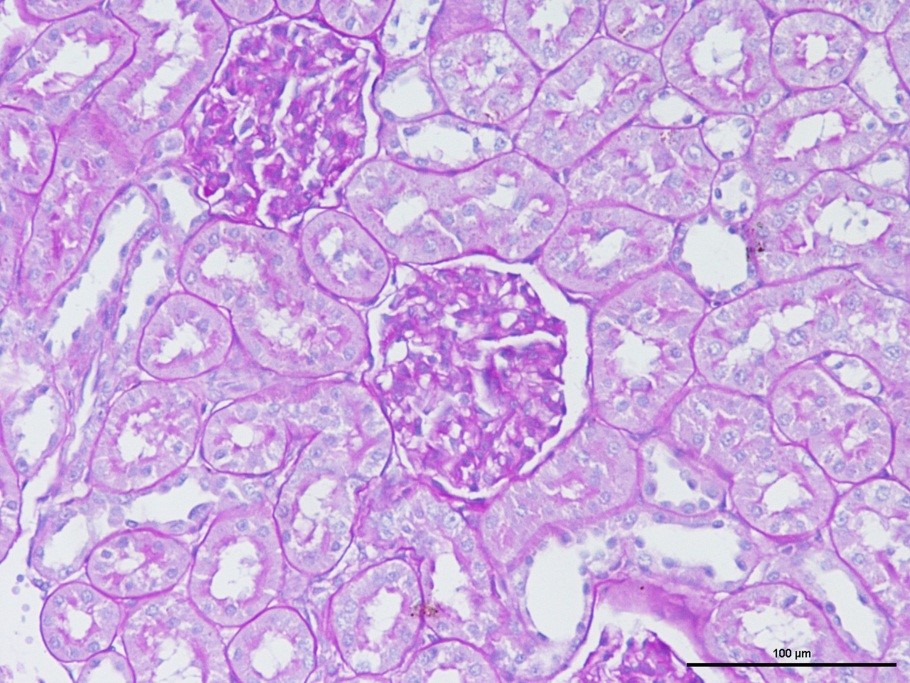

大鼠腎組織PAS染色效果

概述:該染色方法可用于糖尿病腎病模型,用于顯示腎小球病變中糖原沉積,基底膜增厚。